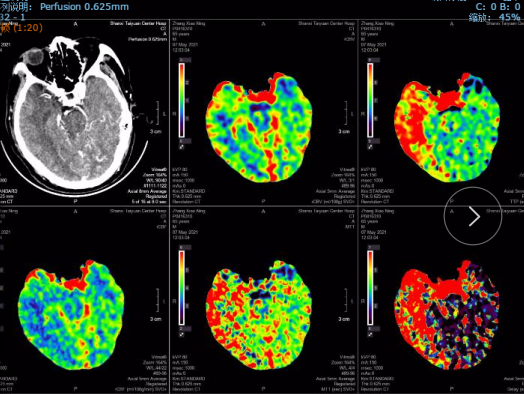

CTP:

右侧基底节区、颞叶、顶叶低灌注区域。

术后8天头颅CT及CTP影像:无出血,右侧半球脑灌注较术前明显改善。